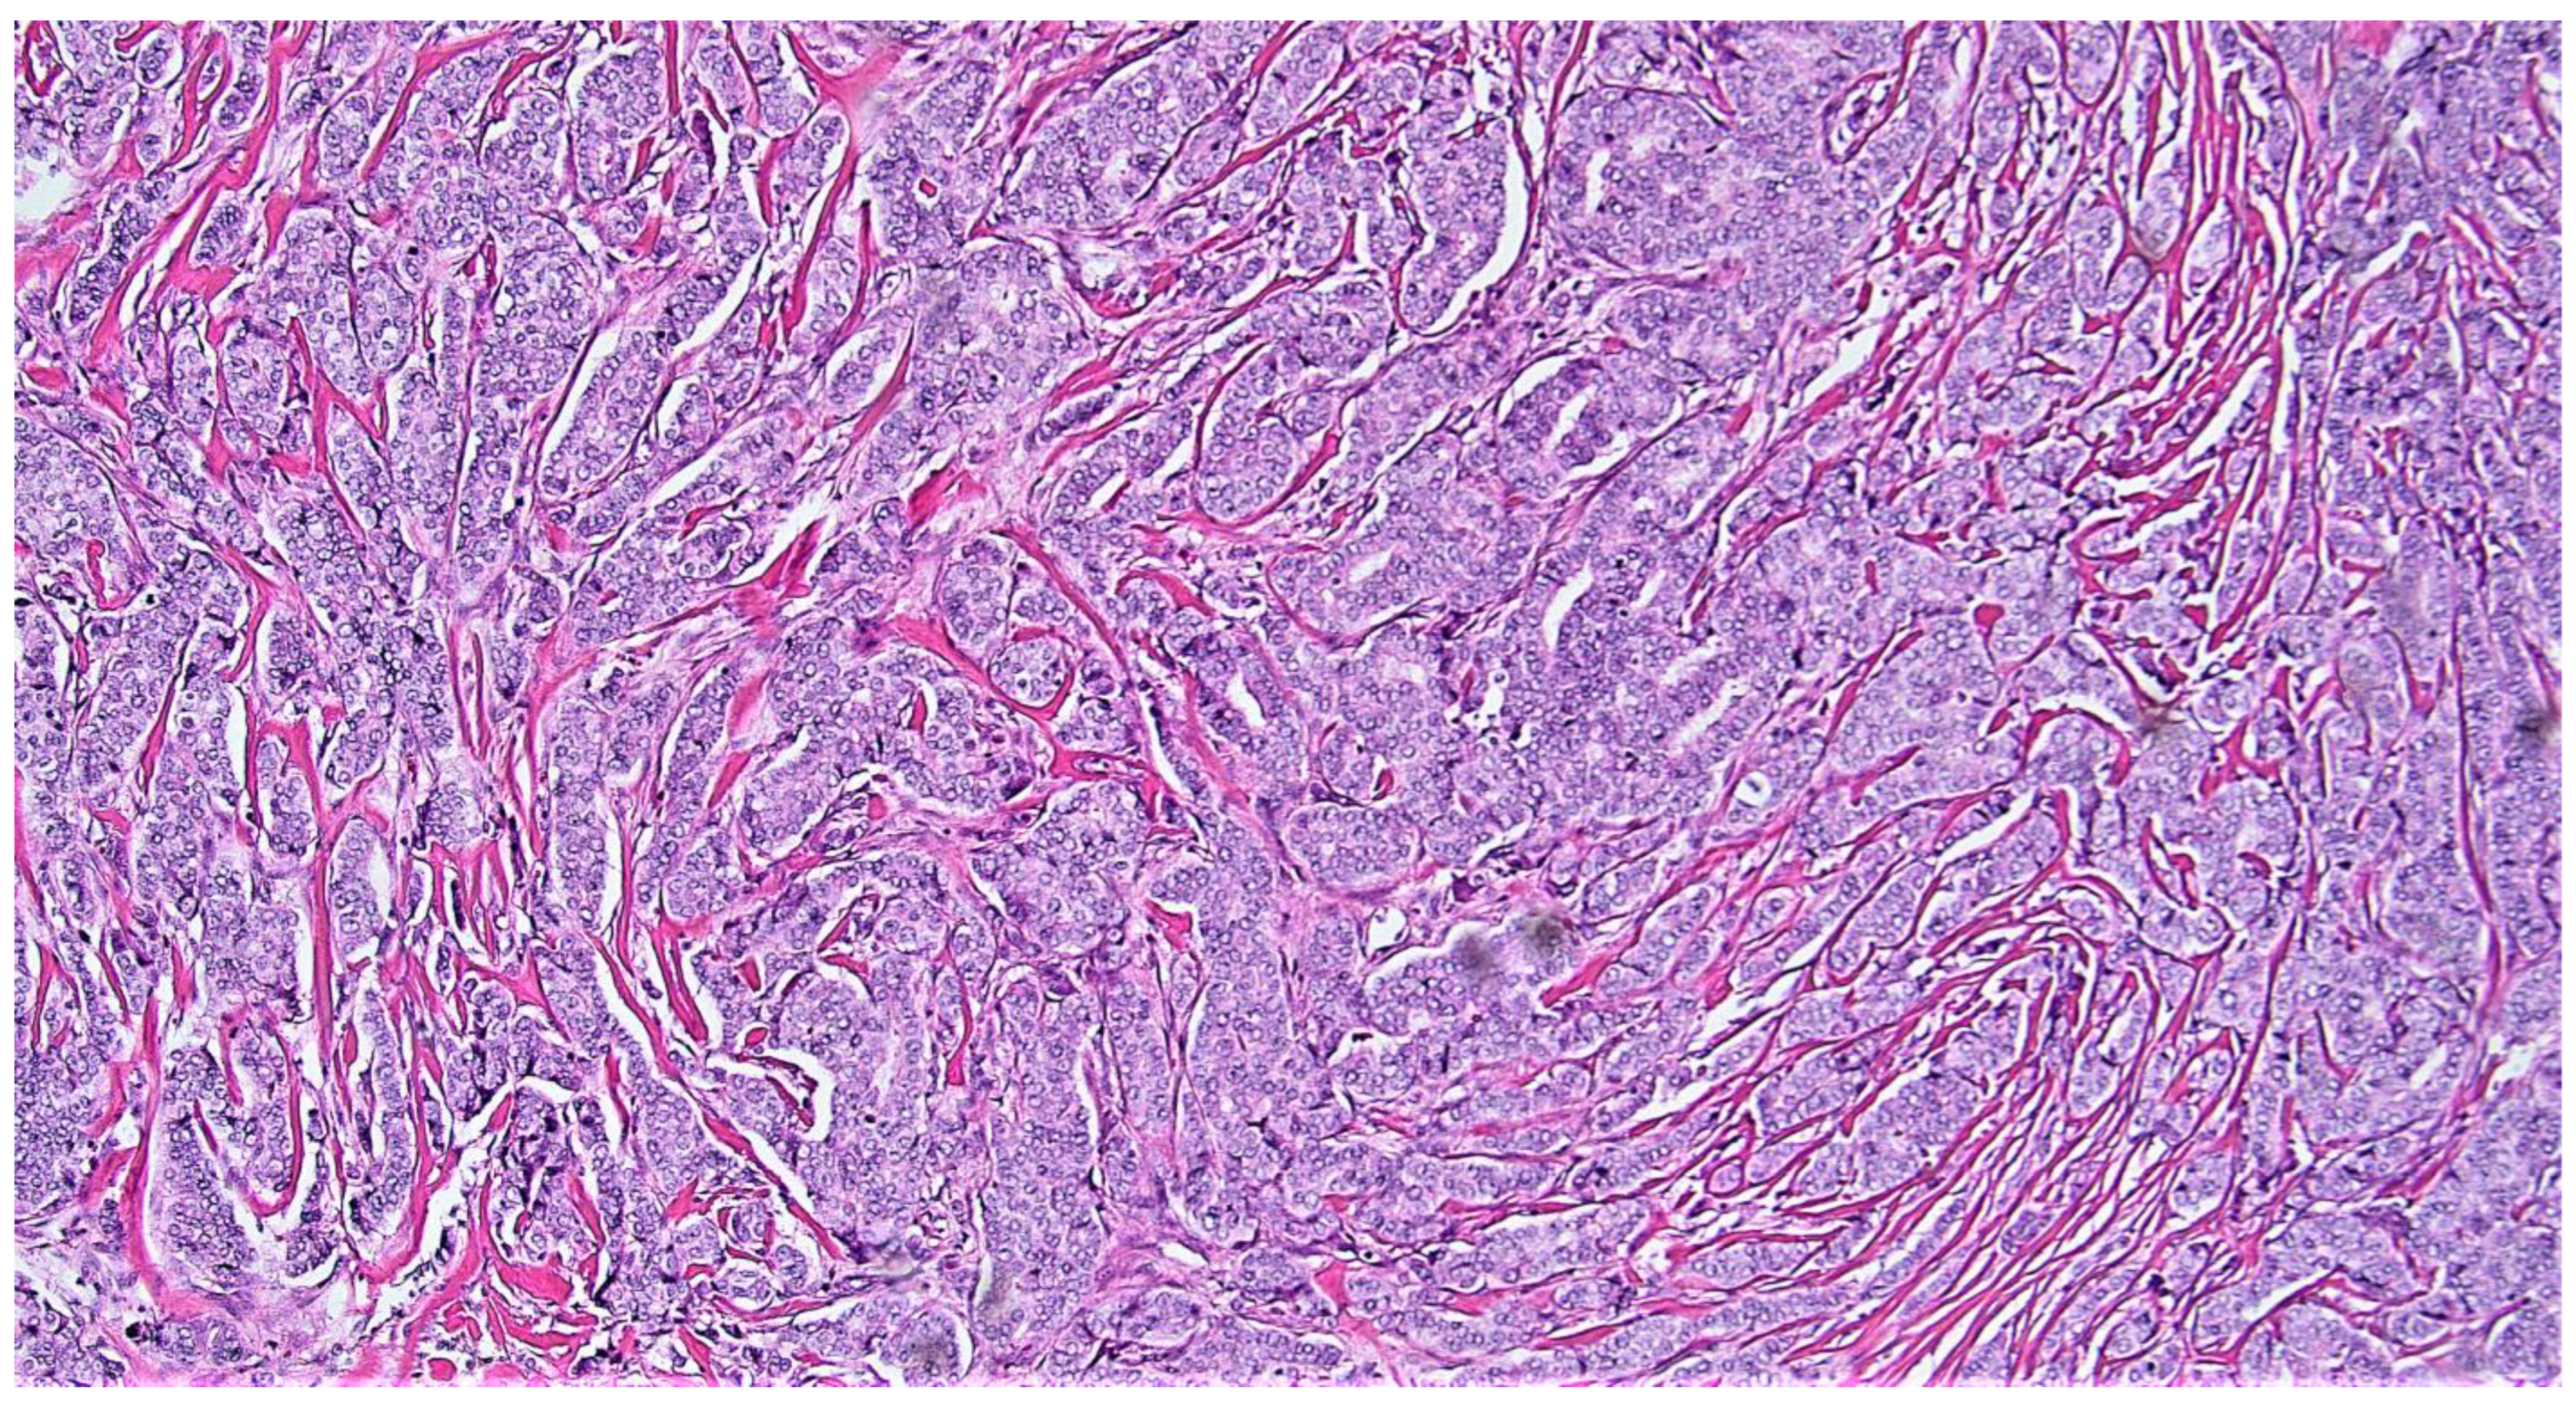

2. Materials and Methods

3. Results

4. Discussion